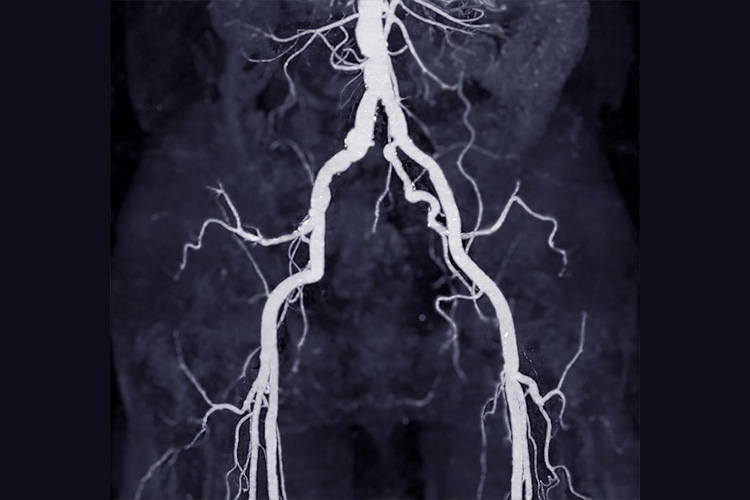

③造影CT検査

心筋梗塞のイメージ

造影剤を静脈注射してCTをとることで、動脈の狭窄や閉塞の有無を診断します。画像を三次元構成することが可能です。動脈瘤の合併や壁在血栓の有無、血管の石灰化も評価可能であり、非常に重要な検査です。